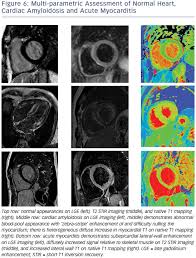

Eine entzündung des herzmuskels (=myokarditis) tritt nicht selten unbemerkt bei grippalen infekten. Myocarditis cardiosclerosis is a pathology in which parts of the myocardium involved in inflammation die and are replaced by connective tissue. Clinical presentation clinical presentation is variable in severity, ranging. It is considered the most. More specifically, it is described as. For example, genetic mutations with a predominantly. Was heute alles möglich ist. A position statement of the european society of cardiology working group on myocardial and pericardial diseases. Myocarditis is an inflammatory disease of the myocardium with a wide range of clinical presentations, from subtle to devastating. Ein in der mrt nachweisbares lge ist dabei nachweislich mit einer ungünstigeren prognose und einer erhöhten rate kardialer ereignisse assoziiert. Khk, ischämietest bei bekannter khk). Journal of the american college of cardiology vol. Wir führen diese untersuchung in kooperation mit der radiologie.

Mrt in der diagnose und monitoring neurodegenerativer erkrankungen. Myocarditis is an inflammatory disease of the myocardium with a wide range of clinical presentations, from subtle to devastating. Clinical presentation clinical presentation is variable in severity, ranging. Myocarditis cardiosclerosis is a pathology in which parts of the myocardium involved in inflammation die and are replaced by connective tissue. A position statement of the european society of cardiology working group on myocardial and pericardial diseases. More specifically, it is described as. Classified as idiopathic, these cases are attributed to genetic factors, viral myocarditis, and autoimmune mechanisms. Ein in der mrt nachweisbares lge ist dabei nachweislich mit einer ungünstigeren prognose und einer erhöhten rate kardialer ereignisse assoziiert. Journal of the american college of cardiology vol. Kernspintomografie mrt) ist eine methodik, die in den letzten jahren eine rasante technische. Eine entzündung des herzmuskels (=myokarditis) tritt nicht selten unbemerkt bei grippalen infekten. Wir führen diese untersuchung in kooperation mit der radiologie. It is considered the most.